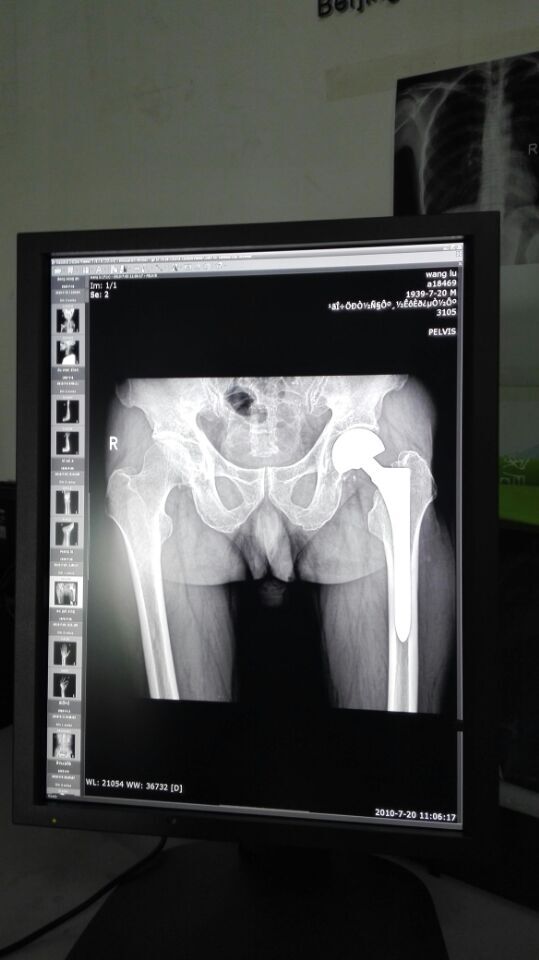

3MP醫(yī)療診斷型灰階液晶顯示器

?這用於PACS CR DR DSA X-PAY等醫(yī)療設(shè)備

?精準(zhǔn)的DICOM設(shè)定和伽馬校準(zhǔn) 人性化OSD菜單